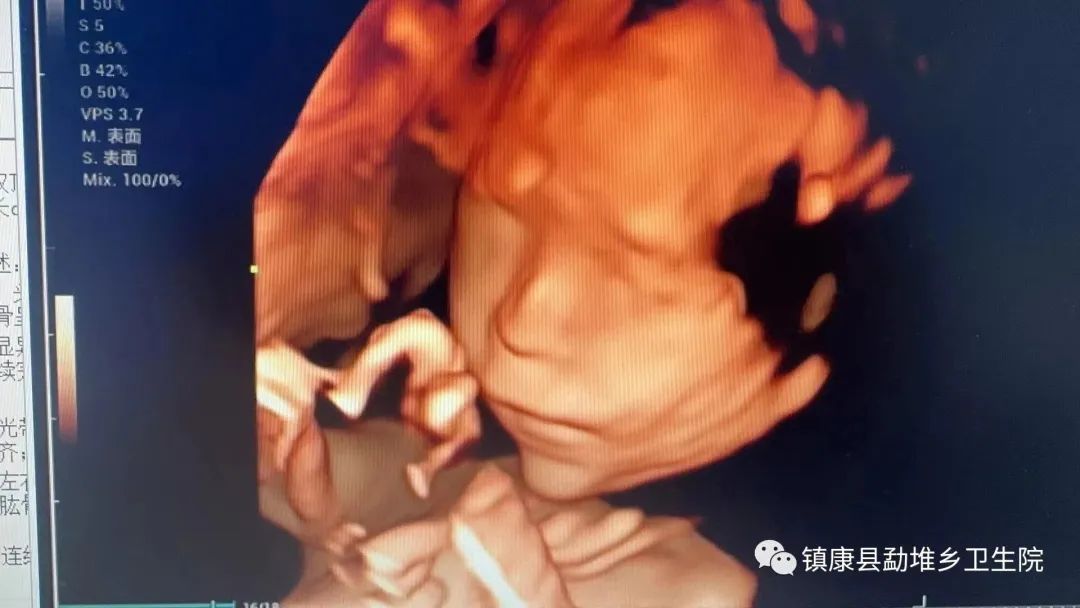

四维影像

帮扶专家张主任(副主任医师)正在勐堆乡卫生院进行 四维彩超、NT检查